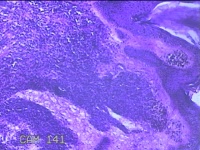

颈后肿物

性别

男

年龄

40岁

临床诊断

汗疱疹;疣

一般病史

颈部发生1cm大小乳头状皮色丘疹多年。

标本名称

大体所见

灰白粉红色带皮肤样肿物1x0.8x0.3cm一个,表面光滑,肿物表面有少许毛发,切开肿物呈实性,切面灰白粉红色,质软。